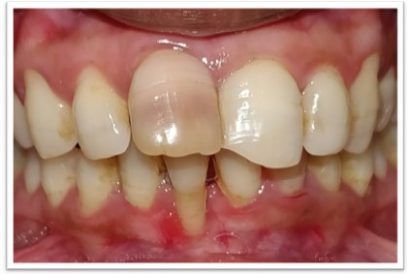

Patient Name:Anil Jagtap

Tooth Involved : 22

Diagnosis : Ellis Class IV Fracture With 22

Treatment : Root Canal Treatment 22

Restoration: Cast Post And Core With Porcelain Fused To Metal Crown.

Before